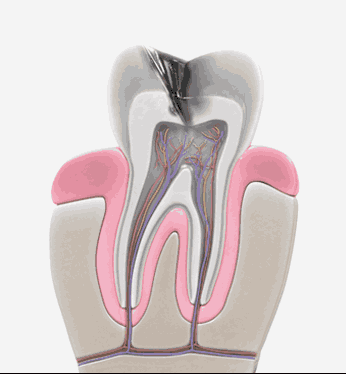

신경치료는 충치가 신경까지 번진 경우, 치아가 부러져 신경이 노출된 경우, 뿌리에 염증이 생긴 경우 진행하는 치료방법입니다. 신경관이 막혀있거나 신경관에 post가 박혀있는 경우 치료의 난이도는 매우 어려워 지며 많은 분들이 발치를 권유 받습니다. 청담뷰치과는 자연치아살리기 진료를 전문적으로 다뤄왔기에 막힌 신경관을 찾거나 만곡이 심한 신경관을 다루는 치료까지 성공적인 결과를 제공해 드릴 수 있습니다.